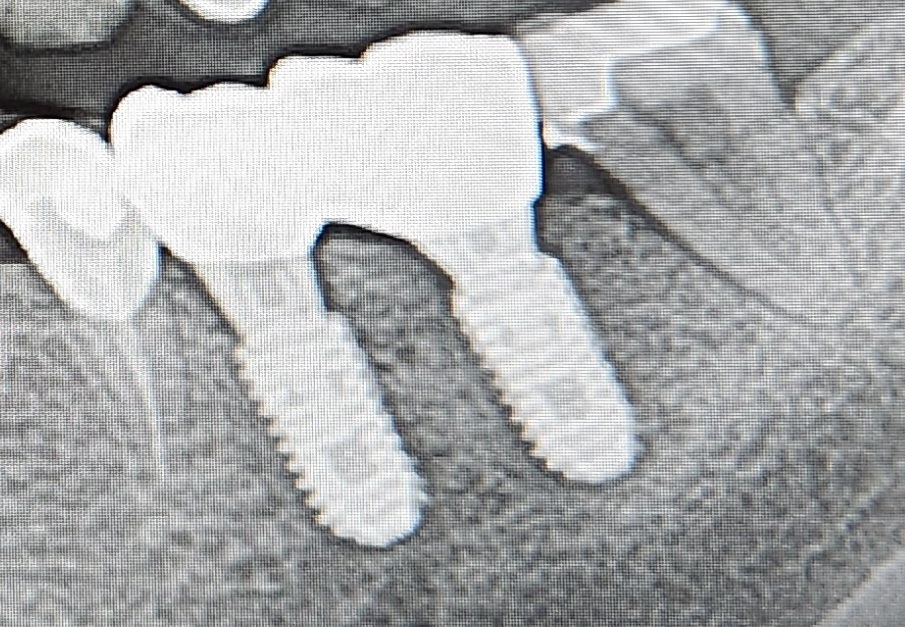

임플란트 두개를 연결해서 크라운 하는게 보편적인가요?

연결한 가운데 사이에 음식도 들러붙고 통증도 있네요 차라리 뚤려있으면 관리가 잘 될것 같기도 하고..각각 하나씩 연결했음 하는 아쉬움이 남는데 이렇게 연결하는게 튼튼하고 당연한거라고 하니 할말이 없네요.그리고 음식물 씹을때 통증이 있는데 적응하느라 그런걸까요ㅠ

일반적으로 임플란트는 묶어서 보철물을 만듭니다. 사진상으로 보면 임플란트 보다 임플란트 뒤쪽치아가 안좋아 보이네요. 가셔서 검진을 받아보세요.

임플란트를 서로 묶어 연결해 힘을 분산시켜 유지력 측면에서 유리하고 저작력에 더 잘 견디기 때문에 많이 합니다..음식물 씹을때 통증은 적응되면 좋아질수 있습니다.